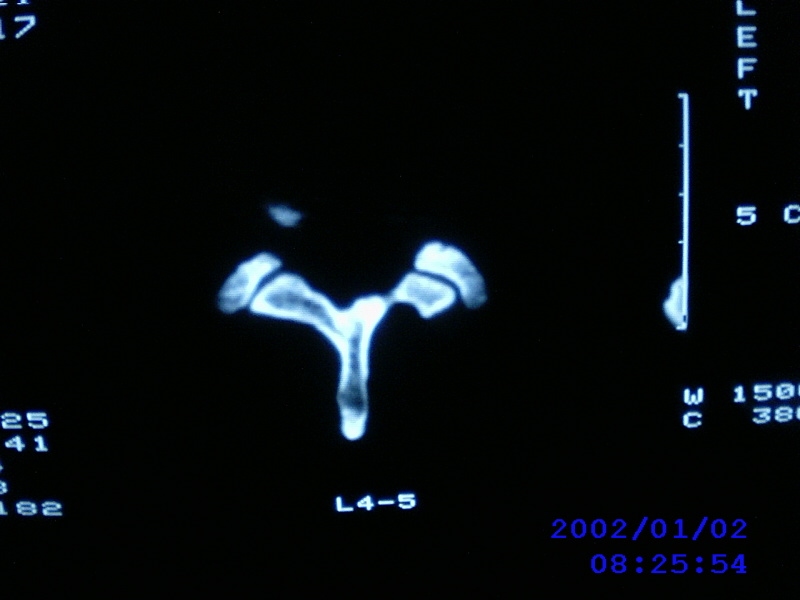

患者,男性,40岁,腰痛伴左下肢疼痛、麻木6年。5年前做过腰椎间盘手术,具体是哪个位置病人记不清了。

我拍的是l4-5、l5-s1

1)l4/5及l5/s1左侧椎板术后改变。2)l5/s1椎间盘突出,l5椎体下缘许莫氏结节。3)l4/5椎间盘膨出并突出。4)l3/4椎间盘膨出。

1)l4/5及l5/s1左侧椎板术后改变。2)l5/s1椎间盘突出,l5椎体下缘许莫氏结节。3)l4/5椎间盘膨出并突出。

1)l4/5及l5/s1左侧椎板术后改变。2)l5/s1椎间盘突出,l5椎体下缘许莫氏结节。3)l4/5椎间盘膨出并突出。4)l3/4椎间盘膨出。支持!